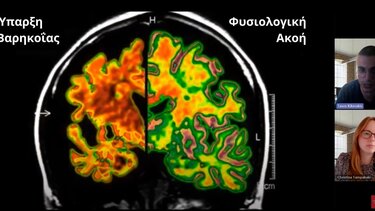

Οι επιπτώσεις της βαρηκοΐας στον εγκέφαλο και οι λύσεις για παιδιά και ενήλικες

Η αποκατάσταση της ακοής συμβάλει στην ανάπτυξη των γνωσιακών ικανοτήτων των παιδιών και την επιβράδυνση της εμφάνισης άνοιας

"Η βαρηκοΐα είναι στην πραγματικότητα ένα νευρολογικό νόσημα, και μάλιστα το πιο συχνό και αφορά 1,5 δις ανθρώπους σε όλο τον κόσμο" υπογραμμίζουν τα μέλη της Επιστημονικής Επιτροπής της Earton Services, Αναστάσιος (Τάσος) Κικεράκης | Επιστημονικός Σύμβουλος | Απόφοιτος Ιατρικής Σχολής - Πανεπιστήμιο Κρήτης και Χριστίνα Ταμπακάκη | Λογοθεραπεύτρια - Κλινική Ακοολόγος με Εξειδίκευση στην Παιδική Βαρηκοΐα | Πτυχιούχος Λογοθεραπείας - ΠΑΠΕΛ | Μεταπτυχιακό Ακοολογίας - UCL (UK), αναλύοντας στο video-podcast που ακολουθεί τους λόγους για τους οποίους η αποκατάσταση της ακοής συμβάλει ουσιαστικά τόσο στην ανάπτυξη των γνωσιακών ικανοτήτων των παιδιών, όσο και στην επιβράδυνση της εμφάνισης άνοιας στα άτομα μεγάλης ηλικίας.

Μεταξύ άλλων, αναφέρουν ότι το ακουστικό μονοπάτι είναι από τις κινητήριες δυνάμεις που θα οδηγήσουν στην ανάπτυξη του εγκεφάλου στα παιδιά, καθώς η ακοή εμπλέκεται άμεσα στην ανάπτυξη της ομιλίας και όχι μόνο.

Από την άλλη πλευρά, όπως επισημαίνεται, μελέτες έχουν δείξει ότι η ακουστική αποκατάσταση στους ενήλικες επιβραδύνει την απώλεια σκέψης και μνήμης κατά 48% σε διάστημα τριών ετών.